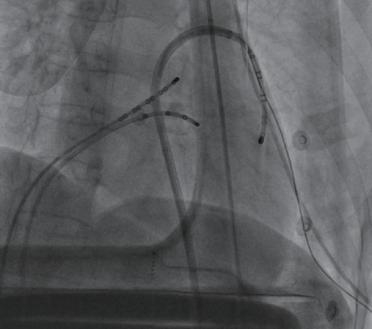

(5)经8F血管鞘送入二十极电极导管,以Velocity导管指引,在三维标测系统下行心外膜基质标测,提示室速来源晚电位(如左心室游离壁或右心室游离壁)后,起搏量化推测出心动过速通道,Turbo模式匹配出折返环,心动过速下标测精准的理想消融靶点(图2-4-2)。

图2-4-2 心外膜下标测靶点